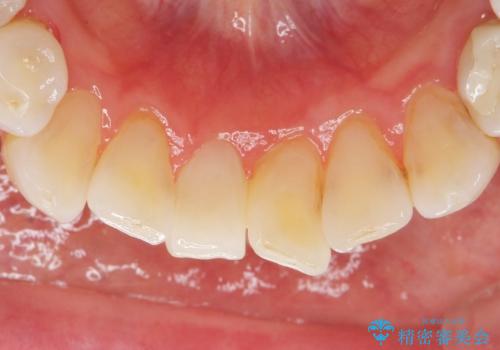

ブリッジとクラウンの自然な仕上がりと咬み心地に喜んで下さいました。

精密な根管治療により、下の前歯の歯ぐきにできていた瘻孔もなくなりました。

右上④3②ブリッジ:オールセラミッククラウン スタンダード

右下1クラウン:オールセラミッククラウン エコノミー